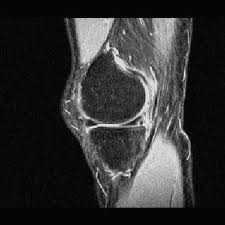

4-Each meniscus appears as a triangle with hypo intense signal (do not contain water), any intensity seen inside meniscus should be considered abnormal.

5-Each meniscus appears in MRI image formed from anterior horn and posterior one if it is seen in its medial parts while if it is cutted laterally, it will be seen as one unit (body) as seen in the diagram below.

*The most important differentiation is that the anterior and posterior horns of the lateral meniscus are equal in size, while in the medial meniscus the posterior horn is always bigger than the anterior horn.

| Lateral meniscus |

| Medial meniscus |

| Meniscial body |

-Take care that just behind the posterior horn of the lateral meniscus there is the tendon of popliteus muscle which could be mistaken as a part of the posterior horn(Remember also that the length of the posterior horn is equal to the anterior horn of the lateral meniscus, so look to the posterior horn, if it is in the same size as the anterior horn, this means that the black area behind it is popliteus tendon and vice versa.